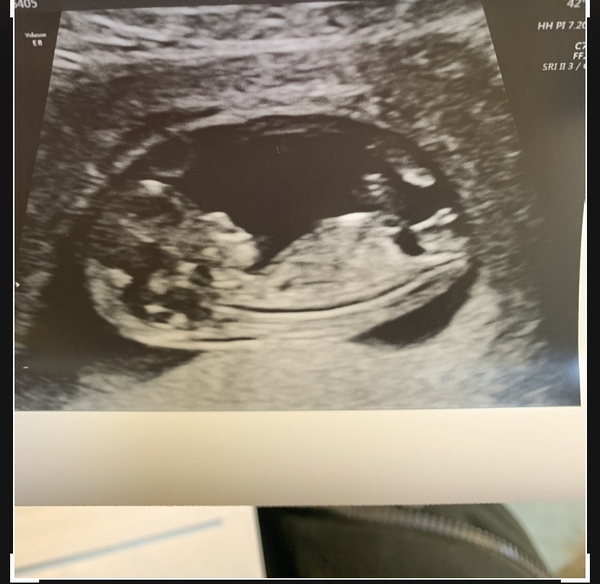

All was perfect!!! Wriggling around so much,

I’m in shock I’m so happy and overwhelmed

@Helensss fabulous pic! So pleased to hear your happy news. Are you going to share with some family and friends now or wait a little while longer? X

@Helensss CONGRATULATIONS. beautiful clear picture. done with screening? or not having it done? hugs

Thank you so much ❤️ I had my bloods taken for the screening so should find out in a week or so, I’ve just told my friends and family, waited so long I couldn’t hold it in any longer!! Xx

Yay, congrats @Helensss it’s so exciting isn’t it! Can’t believe we now have to wait another 8 weeks to see our babies! Seems forever!

@Helensss lovely scan pic 😍

@Helensss congratulations! Gorgeous pic hope you’re feeling more at ease after that :)